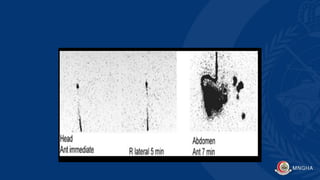

Shunt patency study

1. Variety of CSF shunts are avalible (ventriculoperitoneal,

ventriculoatrial, ventriculopleural, lumboperitoneal) have been

used to treat hydrocephalus.

2. Complications may affect the drainage ,include catheter blockage,

• The diagnosis of shunt patency and adequacy of CSF flow often can

be made by examination of the patient and inspection of the

subcutaneous CSF reservoir.

• When this assessment is uncertain, radionuclide studies with In-111

DTPA or Tc-99m DTPA are useful for confirming the diagnosis.

• Familiarity with the specific shunt type and its configuration is helpful.

For example, the valves may allow bidirectional or only unidirectional

flow ( IMPORTANT).

• Patency of the proximal shunt limb can sometimes be evaluated

before checking distal patency.

• In patients with certain types of variable or low-pressure two-way

valves, the distal catheter is initially occluded by manually pressing on

the neck. The pressure may cause injected tracer to flow into the

proximal limb. Images should show prompt flow into the ventricles,

followed by spontaneous distal flow through the shunt catheter .

• Resistance at the time of injection always indicates malfunction of

the shunt.

• If there is proximal limb malfunction, either no activity will reflux into

the ventricle and there will be rapid transit of the

radiopharmaceutical through the distal shunt into the peritoneal

cavity.